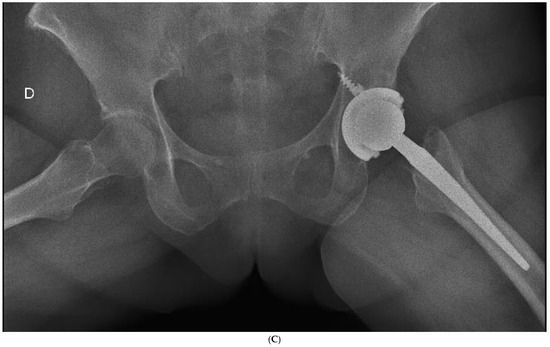

Figure 3.

(A) Preoperative anteroposterior X-ray. Left hip sustained a displaced femoral neck fracture. (B) Postoperative anteroposterior X-ray (SFS group). Both the short stem and acetabular cup appear well osseointegrated and stable at final follow-up. (C) Postoperative lateral X-ray (SFS group). The stem is osseointegrated and there is absence of radiolucent lines at bone-implant interface.